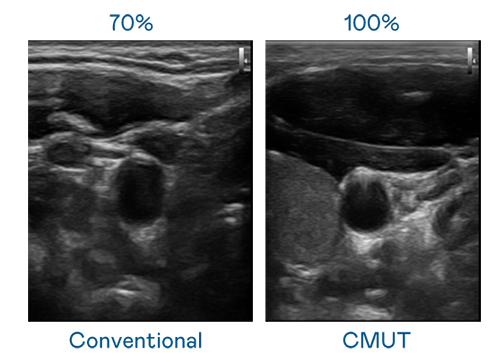

CMUT 技术是一种用电容式微机电元件来产生超音波讯号的技术。与传统 PZT 压电式技术相比,CMUT 频宽增加 30%,更宽频的超音波讯号让影像解析度大幅提升,是实现高影像品质医疗超音波扫描、促进精准医疗发展的关键技术。

超音波影像的解析度高低,首先取决于探头能发出的讯号频宽。梦之城CITY OF DREAMS CMUT 可提供高清晰的超音波讯号,提供高频宽、高灵敏度、影像纹理细节更高的超音波影像,协助医护人员缩短影像判读时间及利用精准的医疗影像进行诊断。